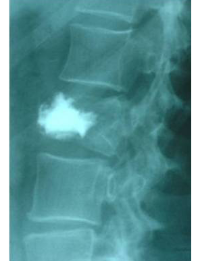

Example Clinical Case: Kyphoplasty

Pre- and post-operative comparison of a cemented kyphoplasty

Female, age 55, compression fracture of L2

Before 1

After 1

Before 2

after 2